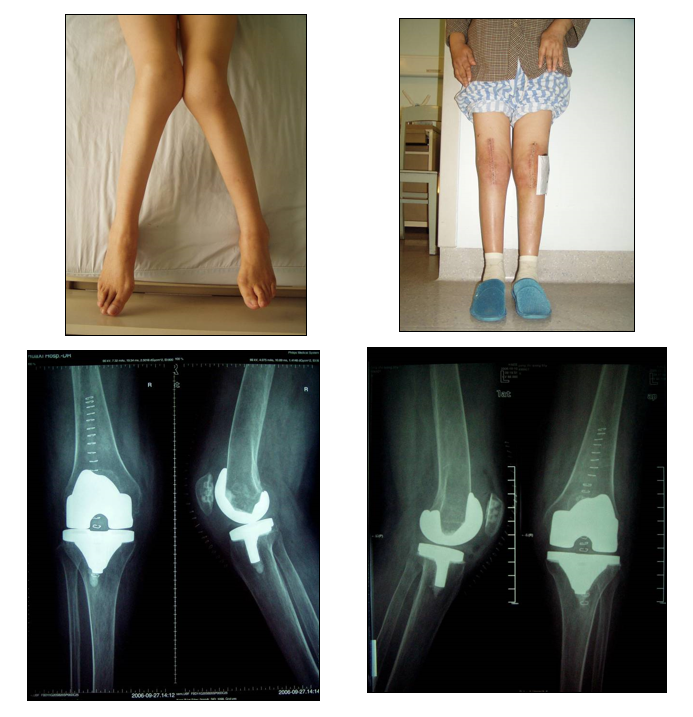

病因源自股骨,外侧髁的远端和后侧发育不良

股骨远端截骨角度≤5°

屈曲位时内侧松弛外侧紧张

确定股骨外旋、适当松解外侧副韧带

伸直位时内侧松弛

行内侧结构的紧缩或外侧结构的松解

术前确定切骨线,胫骨上端切骨线为0°。外侧平台尽量切薄,而内侧平台则切骨很厚。

下肢残留外翻畸形

股骨假体外翻放置